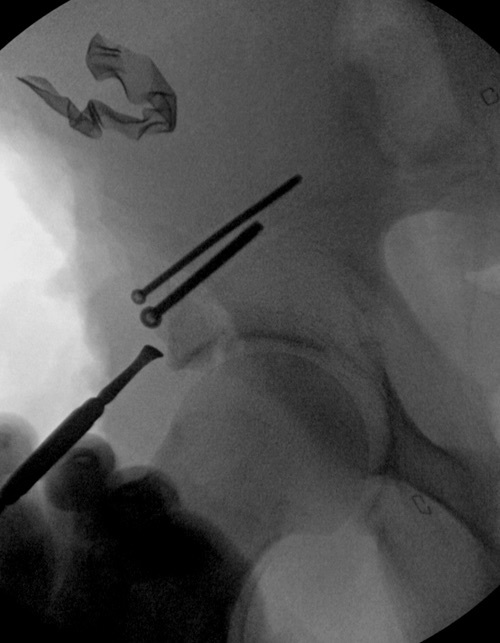

Фиксация переломов передней колонны намного легче, чем остальных переломов вертлужной впадины. Любой доступ: Smith Petersen, Stoppa или ilio-inguinal. Как фиксировать перелом зависит от желания врача, можно пустить пластину по pelvic brim (linea terminalis) или более щадящее из верхнего окна пластиной, а переднюю колонну длинными межколонными винтами.

Здесь пример перелома передней стенки, где сохранен принцип фиксации передней колонны. Для доступа Smith Petersen с остеотомией ASIS. Мышца сарториус отодвинута, и сделана ре-фиксация на свое место винтами. При хорошем обзоре, наличие Farabeuf или Jungblud forceps облегчит репозицию.

привет..сколько зим сколько лет....По моему, пример не совсем корректен...здесь основное -перелом верхнего края впадины (открыто и без вопросов)...всю колонну можно было бы и не фиксировать...она и так хорошо держится...а вот когда мы имеем дело с огроменным куском безымянной кости с кусочком суставной поверхности (очень важным для конгруэнтности)можно и поиграться ...аппарат не такой уж и "огромный" (Вы в курсе)и добиться сращения с активизацией больного очень просто...зато нет риска анестезии...особенно когда все происходит в "степи" (типо ничего нет...)